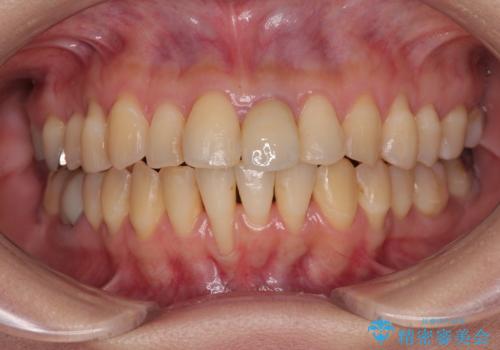

- 他院で矯正治療を終えた結果、下顎前歯の歯肉が退縮してしまい、歯根が見えていることが気になるとのことで来院された患者様です。

歯肉退縮に対して、上顎からの結合組織移植術(CTG)により、歯根の被覆を行うとともに、歯肉の厚みを増すことで将来の退縮リスクを抑制することとしました。

一度の処置で大幅に露出部の被覆に成功しましたが、更なる厚みと被覆を希望されて2回目の処置を行いました。

歯根部周辺の歯肉が非常に分厚くなり、今後の退縮リスクが大きく軽減されました。